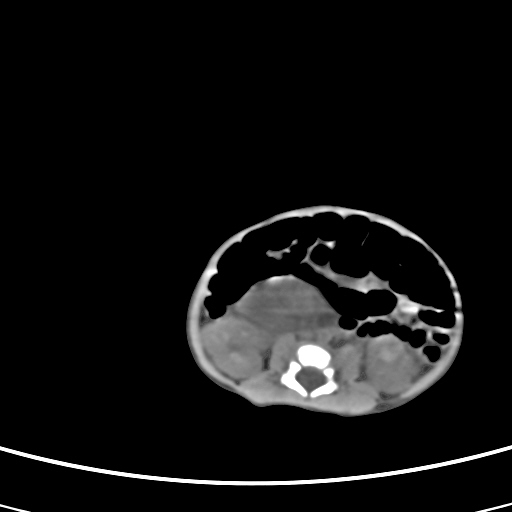

患儿,男性,出生后2天,在胎儿时b超已发现病变,患儿一般情况可。因病变部位偏向于右侧肾上腺区,目前考虑为神经母细胞瘤,不知各位能否支持。

反对定位在右肾上腺区的说法,那么神经母细胞瘤也可以暂时不予考虑。请看下图:

下面这幅图中,似乎可以见到肿瘤的薄包膜,其后与右肾之间的又是什么东西呢?这关系到肿瘤的定位、定性。我考虑病灶是位于肝十二指肠韧带内的畸胎瘤可能性比较大。请各位老师仔细看一下:

病灶巨大,位于右侧肾上腺区,与周围组织分界欠清,内见不规则钙化影,无明显脂肪组织,首先考虑神经母细胞瘤,但畸胎瘤不能排除。

手术结果为畸胎瘤